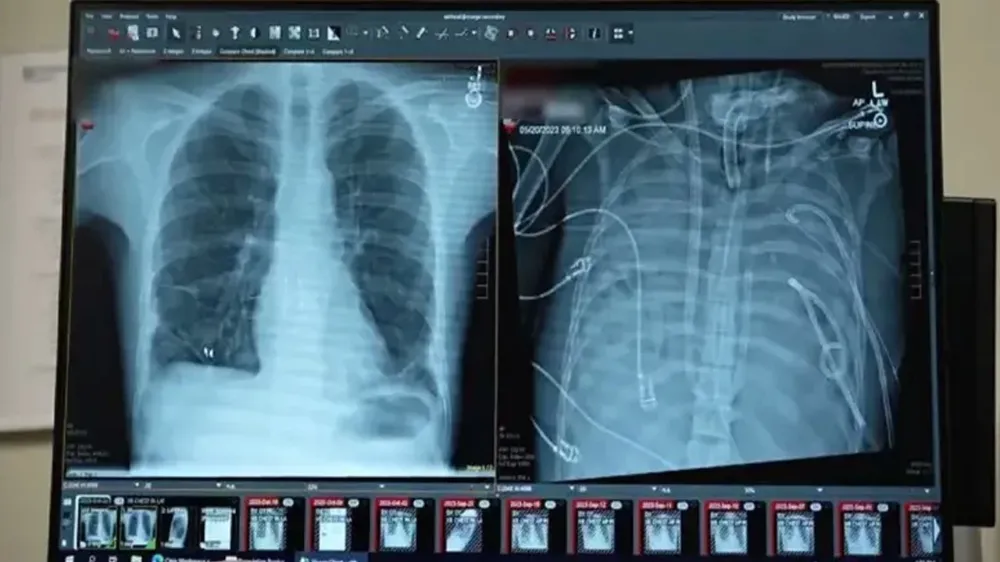

Yapay akciğer teknolojisi, organ nakli bekleyen hastalar için biyolojik donör bağımlılığını sona erdiren tıbbi bir devrime dönüştü. Geliştirilen taşınabilir sistemler, terminal safhadaki hastaların yaşam süresini ve kalitesini kalıcı olarak artırdı.

Geliştirilen yeni nesil yapay akciğer teknolojileri, organ yetmezliği çeken hastalar için biyolojik nakil zorunluluğunu ortadan kaldıran bir dönemi başlattı.

Laboratuvar ortamında optimize edilen bu cihazlar, son klinik testlerde yüksek biyouyumluluk sergileyerek terminal safhadaki hastalar için kalıcı bir çözüm haline geldi.

Geleneksel olarak sadece nakil sürecine kadar "köprü" görevi gören destek cihazları, yerini artık vücut içine tamamen entegre edilebilen ve biyolojik bir organ gibi işlev gören yapay akciğerlere bıraktı.